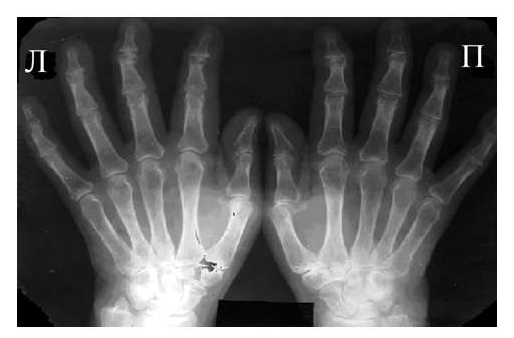

Рис. 3 Сочетание ревматоидного артрита и остеоартроза

Большинство ошибок встречаются при начальных стадиях, особенно при начале РА в пожилом возрасте и сочетании его с остеоартрозом (см. рис. 3). В этом случае для подтверждения диагноза РА и предупреждению случаев его гипердиагностики служит выявление симметричных эрозий в типичных для ревматоидного артрита суставах (запястья, плюснефаланговые, пястно-фаланговые).